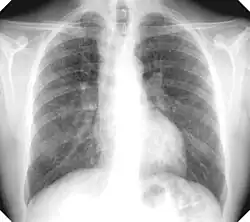

Xray of lungs

Xray of lungs, lighter patches visible

X-rays of patients with simple silicosis (top) and complicated silicosis (bottom)

According to a 2012 study published in Nature, there is a "positive exposure-response between silica and lung cancer".[49] Uranium mining produces silica-laden dust at a free silica rate of 5–15% in Bancroft, significantly less than the Elliot Lake mines which produced ore with 60–70% free silica.[32]: 36

In 1974, the Ontario Workmen's Compensation Board studied 15,094 people who worked in uranium mines in Bancroft and around Elliot Lake for at least one month, between 1955 and 1974. Of those 15,094 people, 94 silicosis cases were found in 1974, of which one was attributed to working a Bancroft mine, i.e. the other 93 were attributed to working in an Elliot Lake mine.[32]: 43, 62, 108

According to the Committee on Uranium Mining in Virginia, mines produce radon gas which can increase lung cancer risks.[50] Miners' exposure to radiation was not measured before 1958 and exposure limits were not enacted until 1968. Risks to miners at Bancroft and Elliot Lake mines were investigated and the official report of that investigation quotes a miner:[32]: 77

The aforementioned 1974 study of 15,094 Ontario uranium miners found 81 former miners who died of lung cancer.[32]: 79  Factoring in predicted lung cancer rate for men in Ontario led to the conclusion that by 1974 there were 36 more deaths than expected attributable to both Bancroft and Elliot Lake mines,[32]: 80  with the additional risk appearing to be twice as high for Bancroft miners compared to Elliot Lake miners.[32]: 348

A study report for the CNSC undertaken by the Occupational Cancer Research Centre at Cancer Care Ontario tracked the health of 28,959 former uranium miners over 21 years and found a two-fold increase in lung cancer mortality and incidence.[1]: 35 table 4  In an article published in The BMJ (journal of the British Medical Association) reported an increase of lung cancer risk; miners who have worked at least 100 months in uranium mines have a twofold increased risk of developing lung cancer.[51] The study is expected to be updated in 2023.[52]